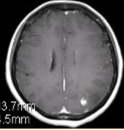

为进一步确诊,MRI增强检查及MRS(Cho升高)结果如下图。可能的诊断为 FSK_MN1_33-2.gif FSK_MN1_33-2-1.gif FSK_MN1_33-2-2.gif